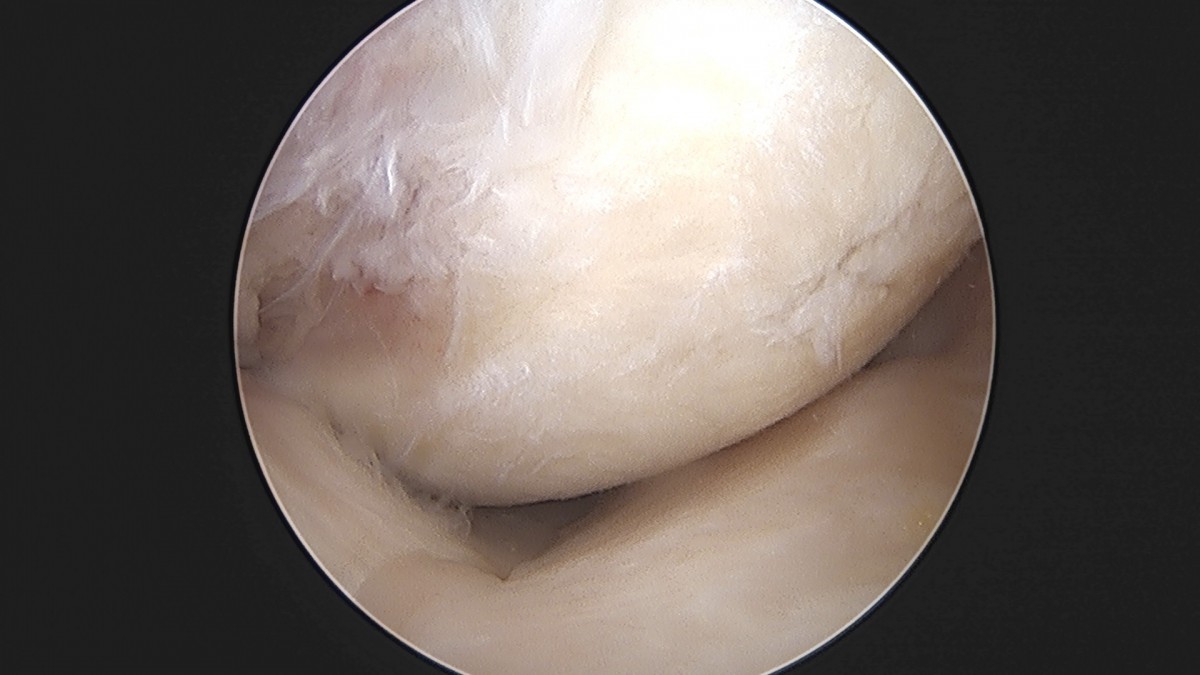

이재상원장님 무릎 반월상 연골판 절제술 박강O 환자

작성자 최고관리자 댓글 0건 조회 381회 작성일 25-09-16 15:47